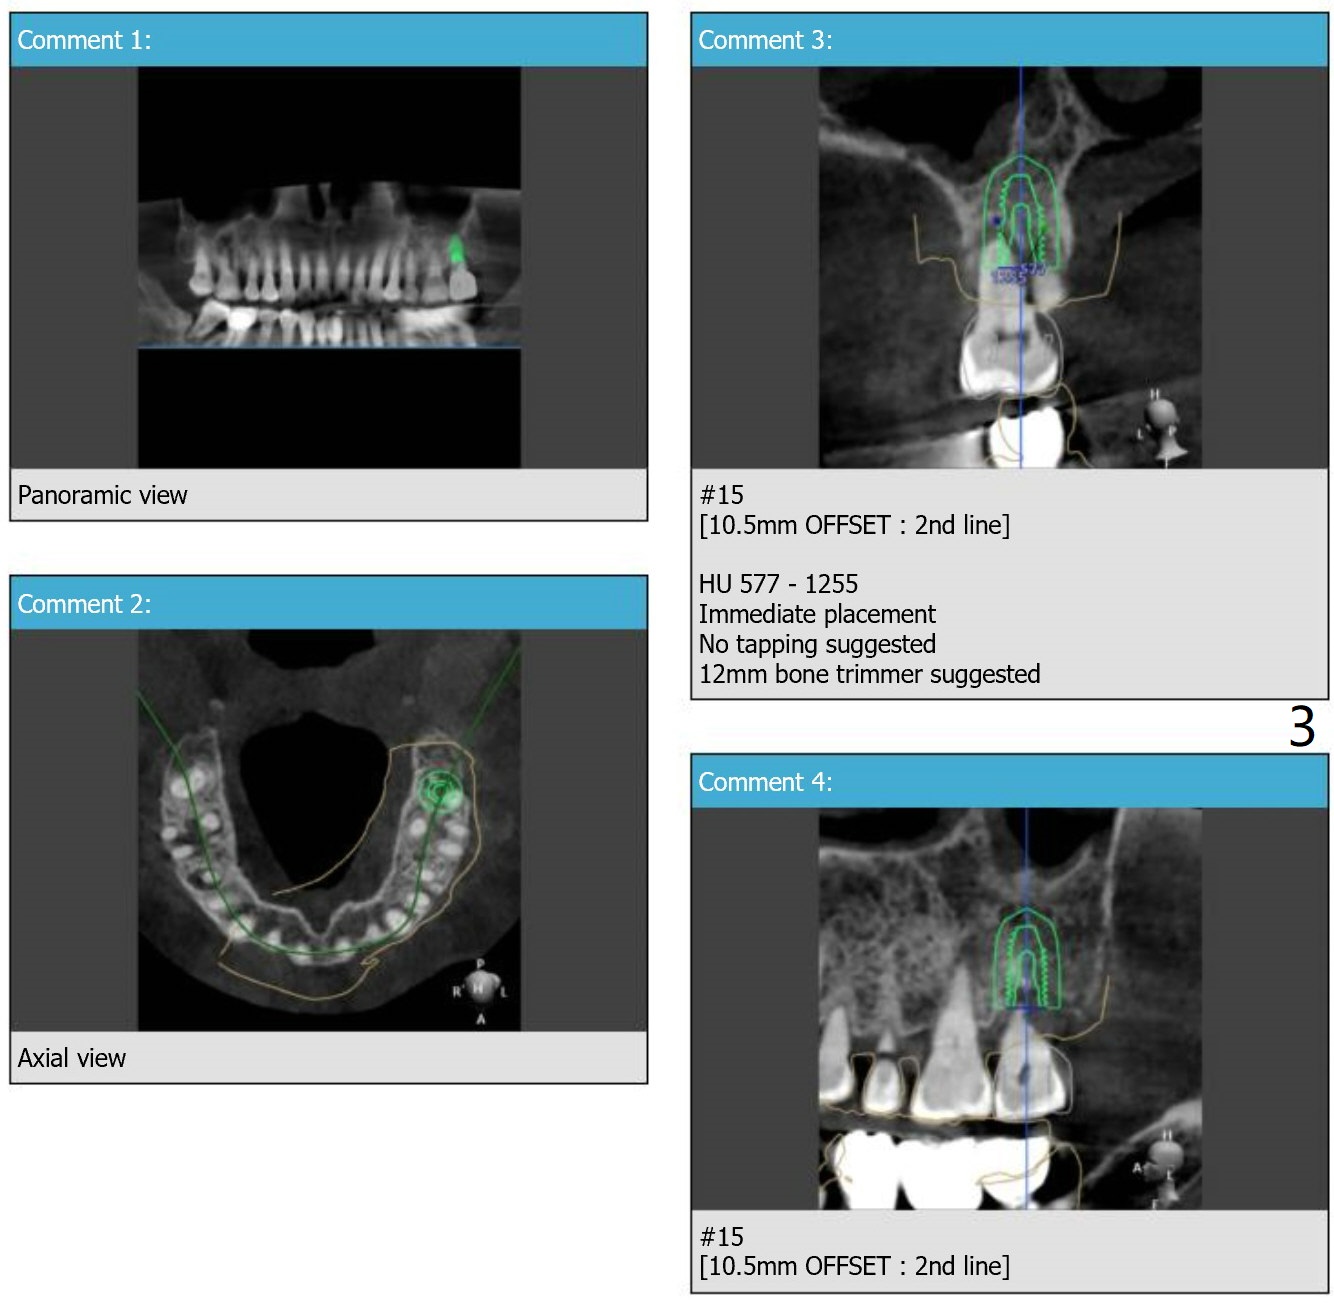

Return to Upper Molar Immediate Implant, Trajectory II

Xin Wei, DDS, PhD, MS 1st edition 01/31/2019, last revision 09/03/2019